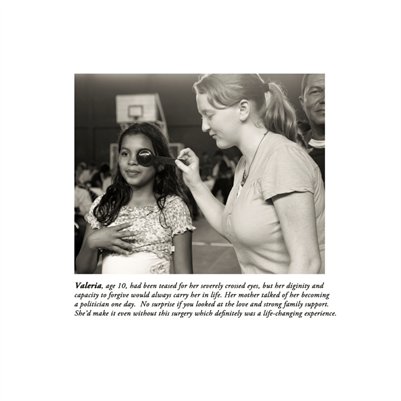

Darkness into the Light. In 2012, The Amazon Project gave eye care to nearly 6000 patients within a 200 kilometer radius of their base in Leticia, Colombia.